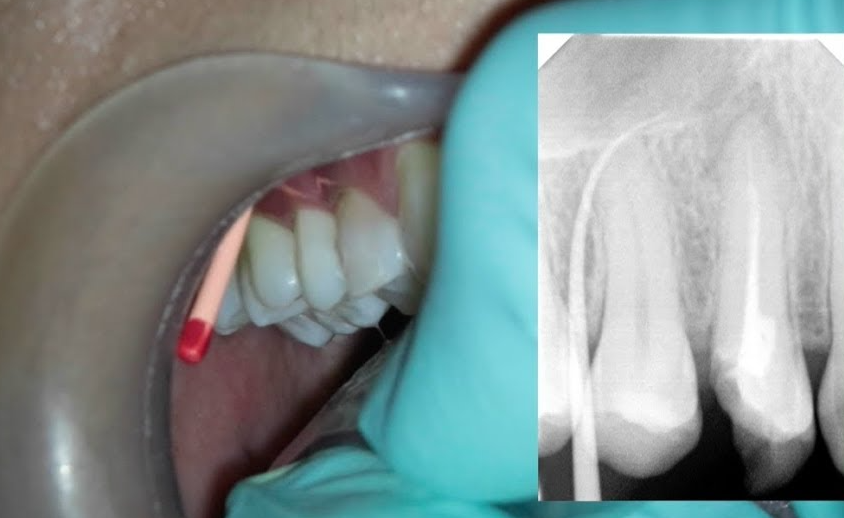

La fistule : définition et trajets

La fistule est un trajet infectieux d’une collection purulente dans l’os alvéolaire, avec orifice d’évacuation.

Trajets fistuleux possibles :

- Transcanalaire : voie naturelle de drainage

- Transligamentaire : rare, avec destruction du ligament alvéolo-dentaire

- Transmuqueuse : abcès s’ouvre spontanément → ostium fistulaire muqueux

- Transcutanée : trajet osseux puis tissulaire, issue à la peau (fistule cutanée)

Examen radiographique

- Cathétérisation du trajet fistulaire avec un cône de gutta-percha pour identifier la dent causale (technique indispensable)

- Zone de raréfaction osseuse diffuse radioclaire

Erreur n°2 — Ne pas cathétériser une fistule pour identifier la dent causale

Pourquoi c’est problématique : Une fistule peut provenir d’une dent éloignée de son orifice cutané ou muqueux (trajet fistuleux long, orienté par les fascias). Traiter la mauvaise dent est une erreur clinique courante.

Bonne pratique : Insérer systématiquement un cône de gutta-percha dans le trajet fistulaire avant la radiographie rétro-alvéolaire. L’image radiographique permettra d’identifier avec certitude la dent causale.

Cas Clinique 3 — L’abcès chronique avec fistule cutanée atypique

Patient : Ahmed, 52 ans, agriculteur, sans suivi dentaire depuis 10 ans. Adressé par son médecin généraliste pour une « plaie chronique au menton » résistante aux traitements locaux.

Présentation : Petite lésion cutanée sous-mentonnière (fistule transcutanée), non douloureuse, avec léger suintement séreux. En intrabuccal, la 31 et la 32 (incisives inférieures) présentent des lésions carieuses étendues. Tests de vitalité négatifs sur la 31. Pas de douleur à la pression.

Problématique identifiée : Après cathétérisation du trajet fistulaire cutané avec un cône de gutta-percha, la radiographie confirme que le trajet mène à l’apex de la 31. Diagnostic retenu : abcès péri-apical chronique fistulisé par voie transcutanée — diagnostic souvent méconnu et pris à tort pour une lésion dermatologique.

Prise en charge :

- Information du médecin généraliste sur le diagnostic odontologique (éviter les prescriptions inutiles de corticoïdes ou d’antibiotiques topiques)

- Traitement endodontique de la 31 en une séance (la fistule assure le drainage naturel)

- Lavage transfistulaire au sérum physiologique

- La fistule cutanée se referme spontanément en 2-4 semaines après élimination de la source infectieuse

Résultat attendu : Fermeture complète de la fistule cutanée et disparition progressive de la lésion de raréfaction osseuse à 6-12 mois. Ce cas illustre l’importance de la cathétérisation fistulaire et la nécessité de toujours rechercher une cause odontologique devant une fistule cutanée de la face ou du cou.